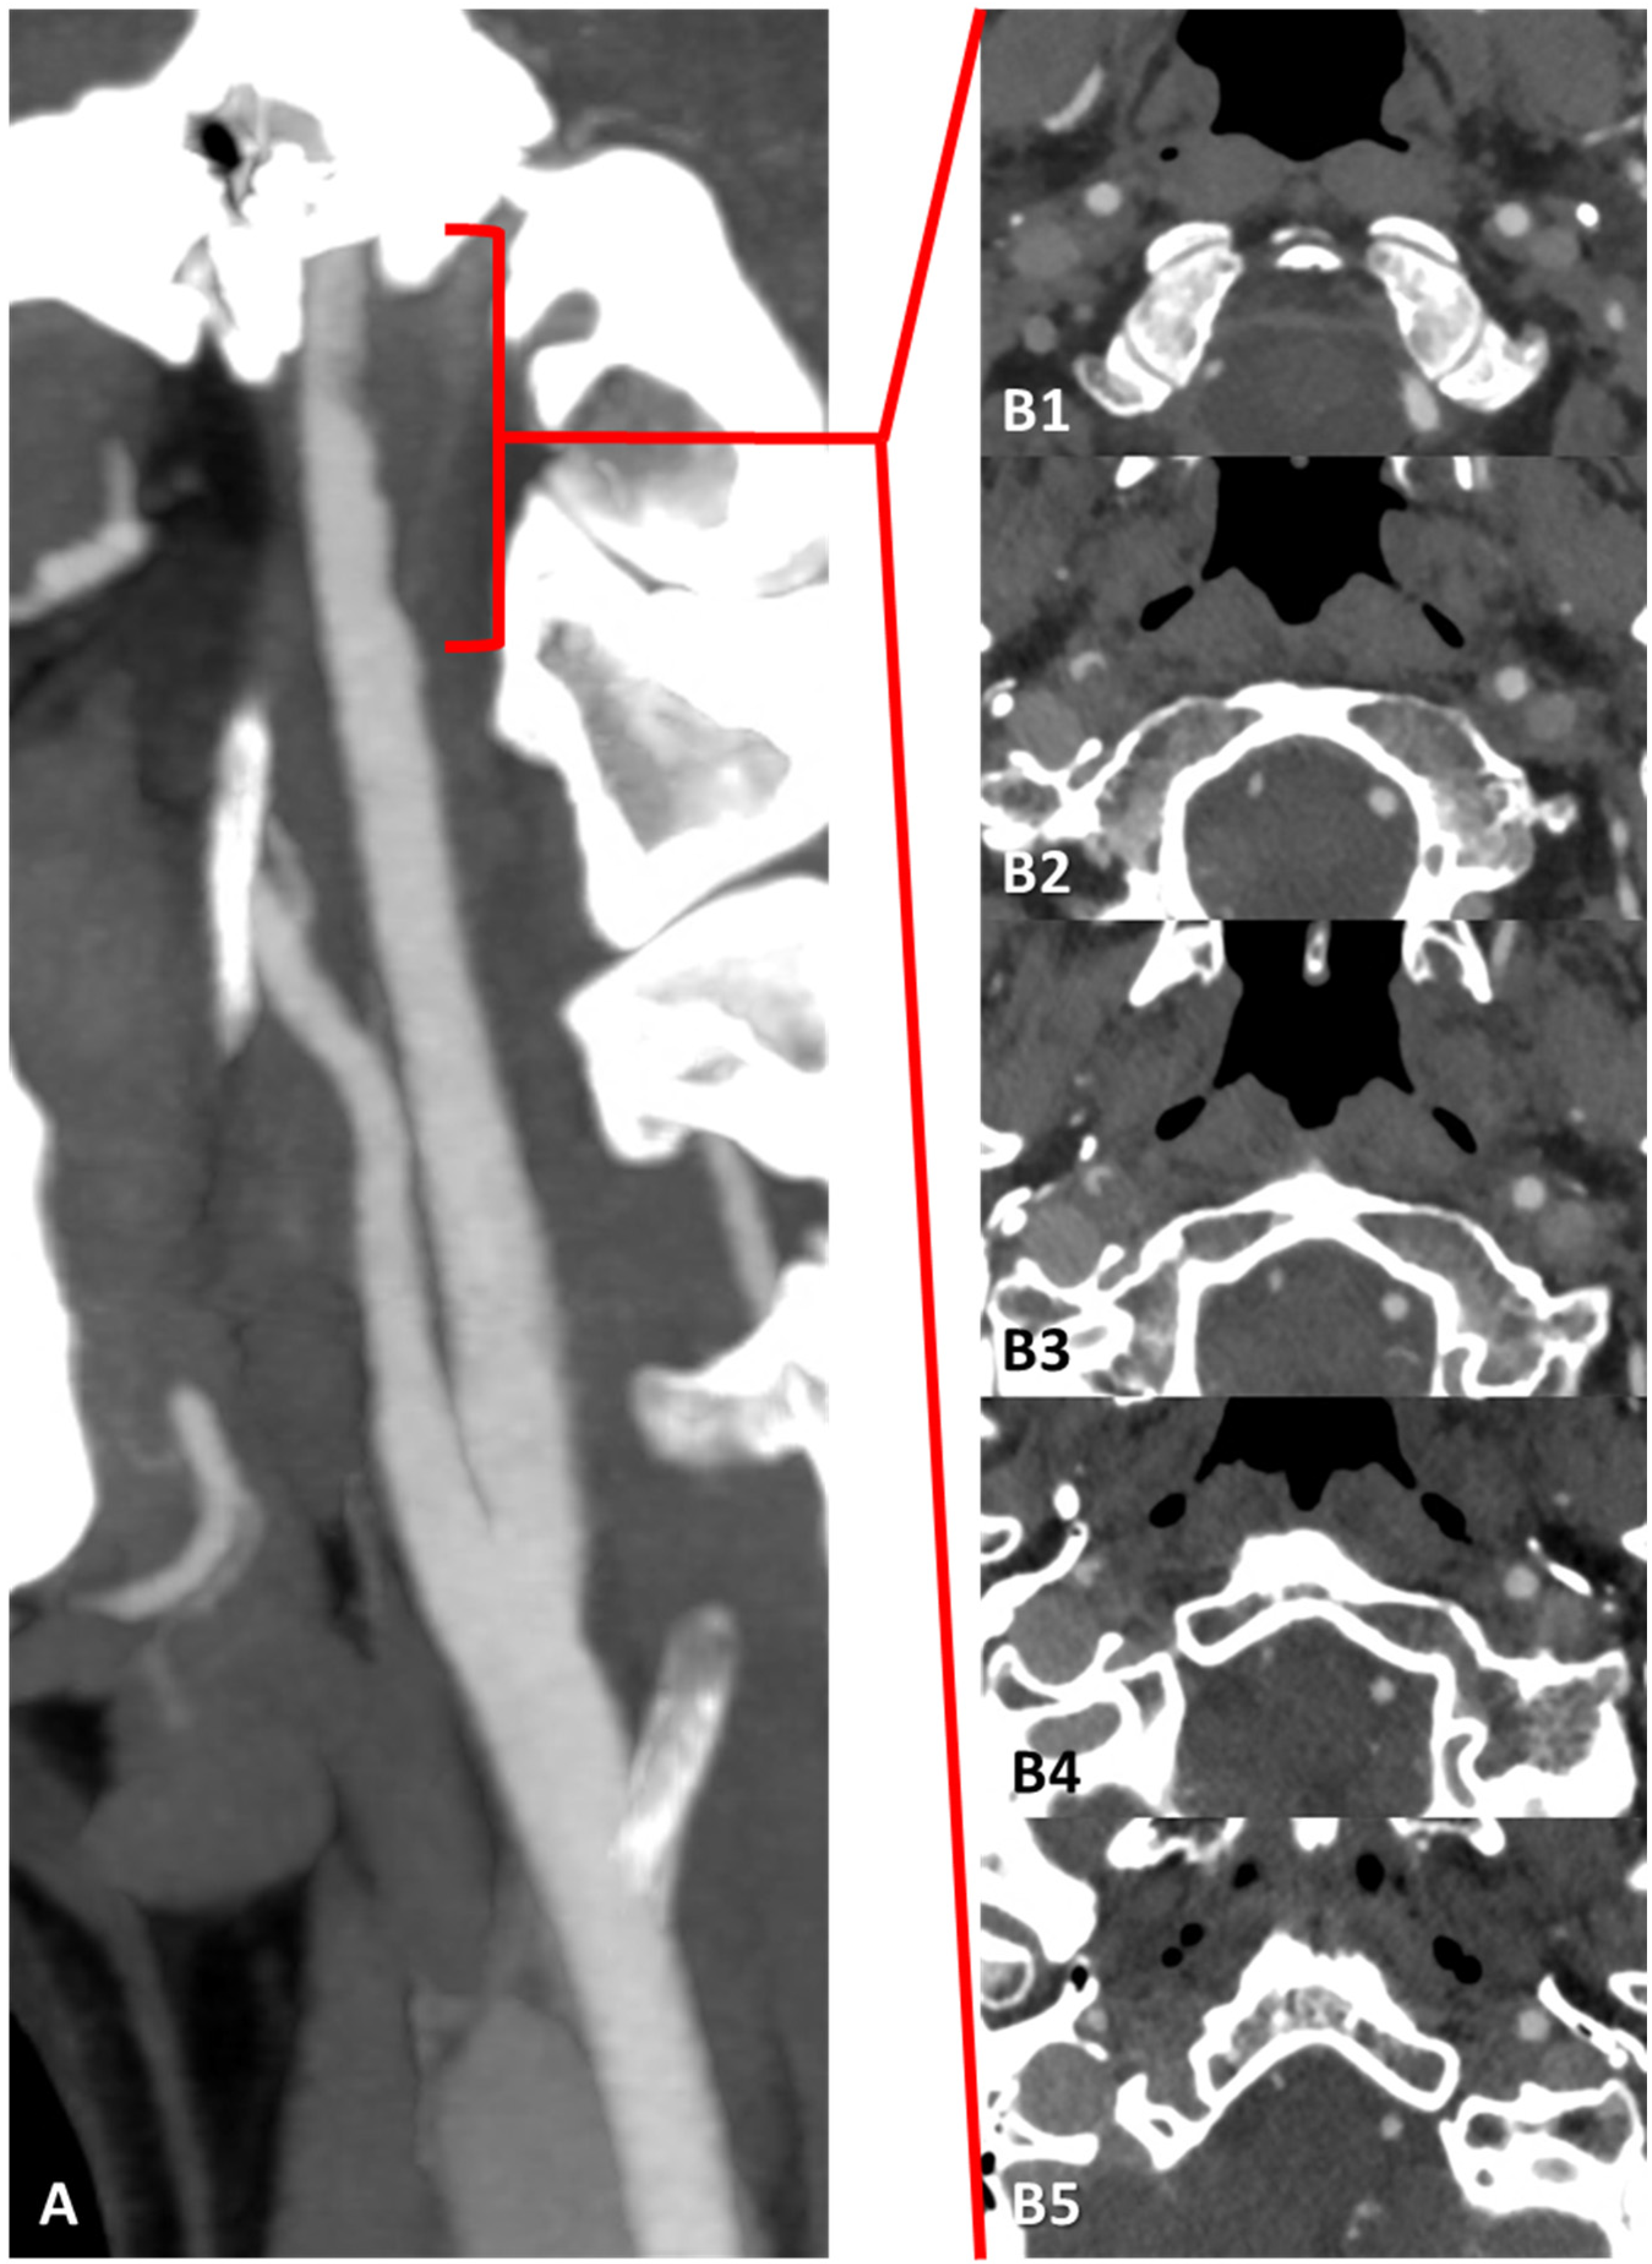

3.1. Case 1

3.2. Case 2